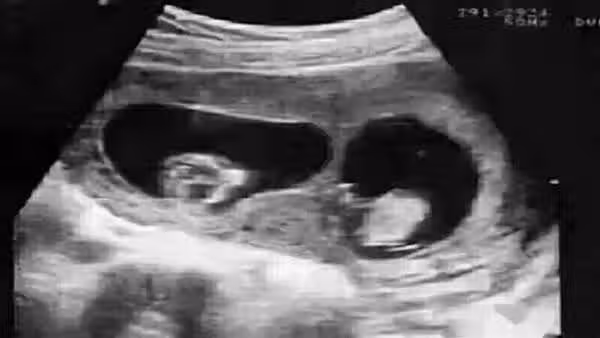

第二種則是,孕期裡媽媽和胎寶寶的血液循環雖然是分開的,但部分母體細胞還是能通過胎盤進入到寶寶身體裡的,自然而然寶寶也可能帶上媽媽的一部分DNA。事實上根據研究發現,有8到9成的準媽媽都有這種現象。並且像是生二胎的時候,媽媽體內攜帶的大寶的基因,就可能進入到二胎的體內。這種也被稱為微嵌合體現象。